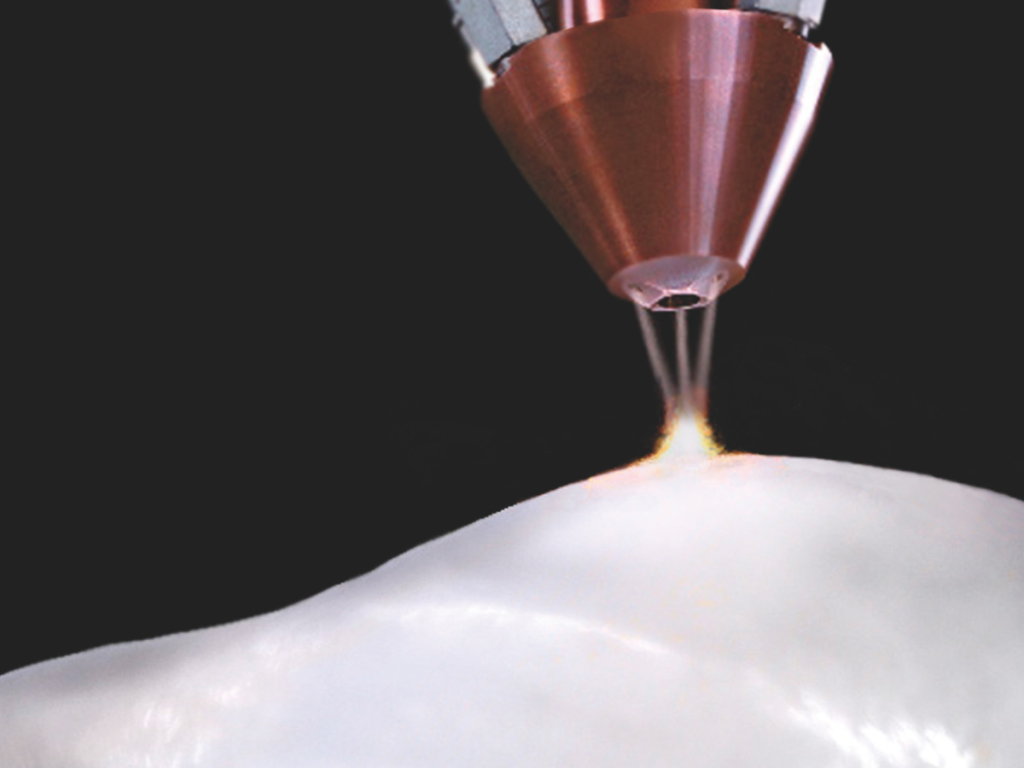

Fruit d’une technologie brevetée de frittage par laser, Ceramir Pediatric Crown associe la résistance des céramiques, l’élasticité de la dentine et la translucidité de l’émail.

Cette combinaison unique imite les caractéristiques naturelles de la dent et amortit les forces masticatoires, protégeant ainsi les dents antagonistes.